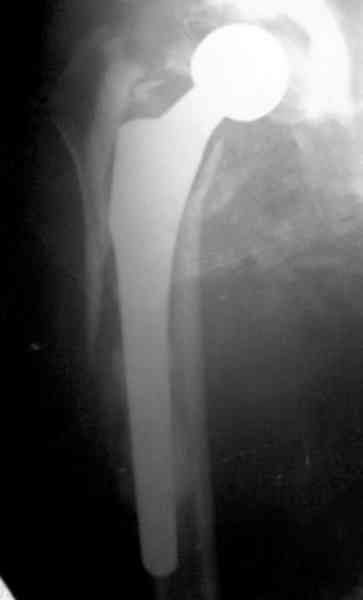

осложненный эндопротез

Представляю вашему вниманию снимки (прошу прошения за качество снимков) больной 48 лет с ревматоидным артритом, которой был сделан тотальный эндопротез справа,

контрольный снимок сделали только на 21 день после операции (№1) и с интервалом 5 дней второй снимок (№2)

Первичные снимки не сохранены.